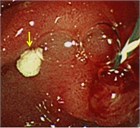

1. 膵管内の結石(膵石)を認めた場合と、膵全体に分布する複数かつびまん性の石灰化を認めた場合は慢性膵炎と診断できる(推奨度1)

1. 加齢現象に伴い膵石が観察される場合がある。

1. 石灰化を伴った膵腫瘍がまれに存在する。